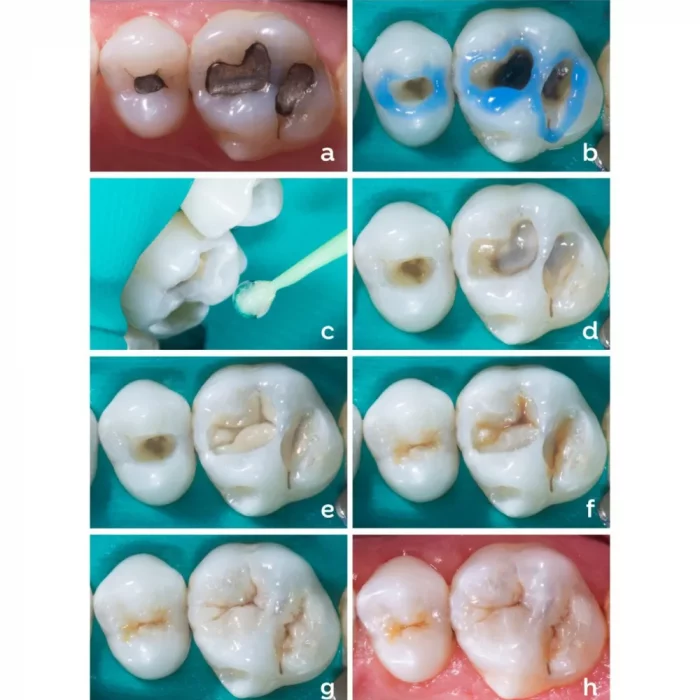

Septodont Endure Nano Hybrid Composite Kit is a comprehensive solution for composite restorations, delivering both efficiency and effectiveness. At its core is a light-cured, radiopaque resin-based dental restorative material, boasting exceptional durability and esthetics. This material ensures reliable performance in both anterior and posterior restorations, providing clinicians with the confidence to deliver long-lasting results. The kit also includes dentin bond and etchant gel, essential components for achieving strong adhesion and optimal bonding to the tooth structure. With these components, clinicians can achieve precise placement, contouring, and finishing, resulting in restorations that seamlessly blend with natural dentition. This user-friendly kit is designed to streamline the restoration process, enabling dental professionals to create esthetically pleasing and durable restorations with ease. Whether addressing minor imperfections or extensive cavities, the Endure Nano Hybrid Composite Kit equips clinicians with the tools needed for successful composite restorations.

- Class I-V restorations

- Restoration of deciduous teeth

- Extended fissure sealing

- Direct veneers